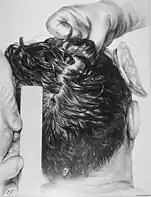

At 7:35 pm EST on November 22, Humes and Boswell removed Kennedy's body from his bronze casket and began the autopsy.[16] Around two dozen people, including military officers, were in attendance.[17][note 3] Admiral Burkley urged the doctors to expedite the autopsy: "all we need is the bullet". Drs. Humes and Boswell, however, argued for a thorough and complete autopsy but temporarily submitted.[23] Medical personnel took photographs—both black and white and color—and X-rays of his head.[23] The X-rays revealed around 40 small bullet fragments along the bullet's trajectory through Kennedy's head, with two large enough to be of interest to investigators. Drs. Humes and Boswell then contacted wound ballistics expert Lieutenant Colonel Pierre Finck of AFIP for assistance.[24] However, they grew tired of waiting and removed the two fragments.[25] They also extracted Kennedy's entire brain and placed it into formaldehyde for later study. Finck arrived soon thereafter and examined the head wound with Boswell and Humes.[26]

- The gunshot wound to the back of the president's head was described by the Bethesda autopsy as a laceration measuring 15 by 6 millimetres (0.59 in × 0.24 in), situated to the right and slightly above the external occipital protuberance. In the underlying bone is a corresponding wound through the skull showing beveling (a cone-shaped widening) of the margins of the bone as viewed from the inside of the skull.[38]

- The large and irregularly-shaped wound in the right side of the head (chiefly to the parietal bone, but also involving the temporal and occipital bone) is described as being about 13 centimetres (5.1 in) wide at the largest diameter.[38]